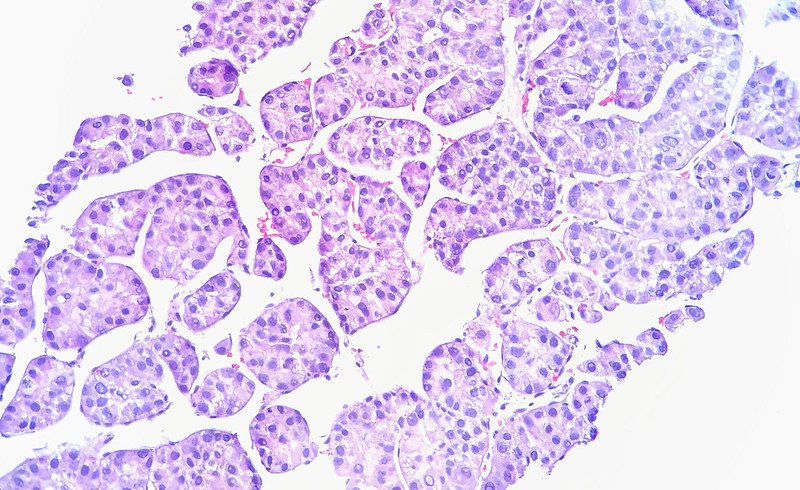

The Oricell cell therapy, Ori-101, is designed to treat advanced cases of hepatocellular carcinoma. It’s an autologous CAR T-therapy, made by harvesting a patient’s immune cells and engineering them in a lab to become targeted cancer fighters. The target of Ori-101 is Glypican-3, or GPC3, a protein that’s highly expressed by liver cancer cells but less so by healthy cells of the organ.

Image by Flickr user Ed Uthman via a Creative Commons license